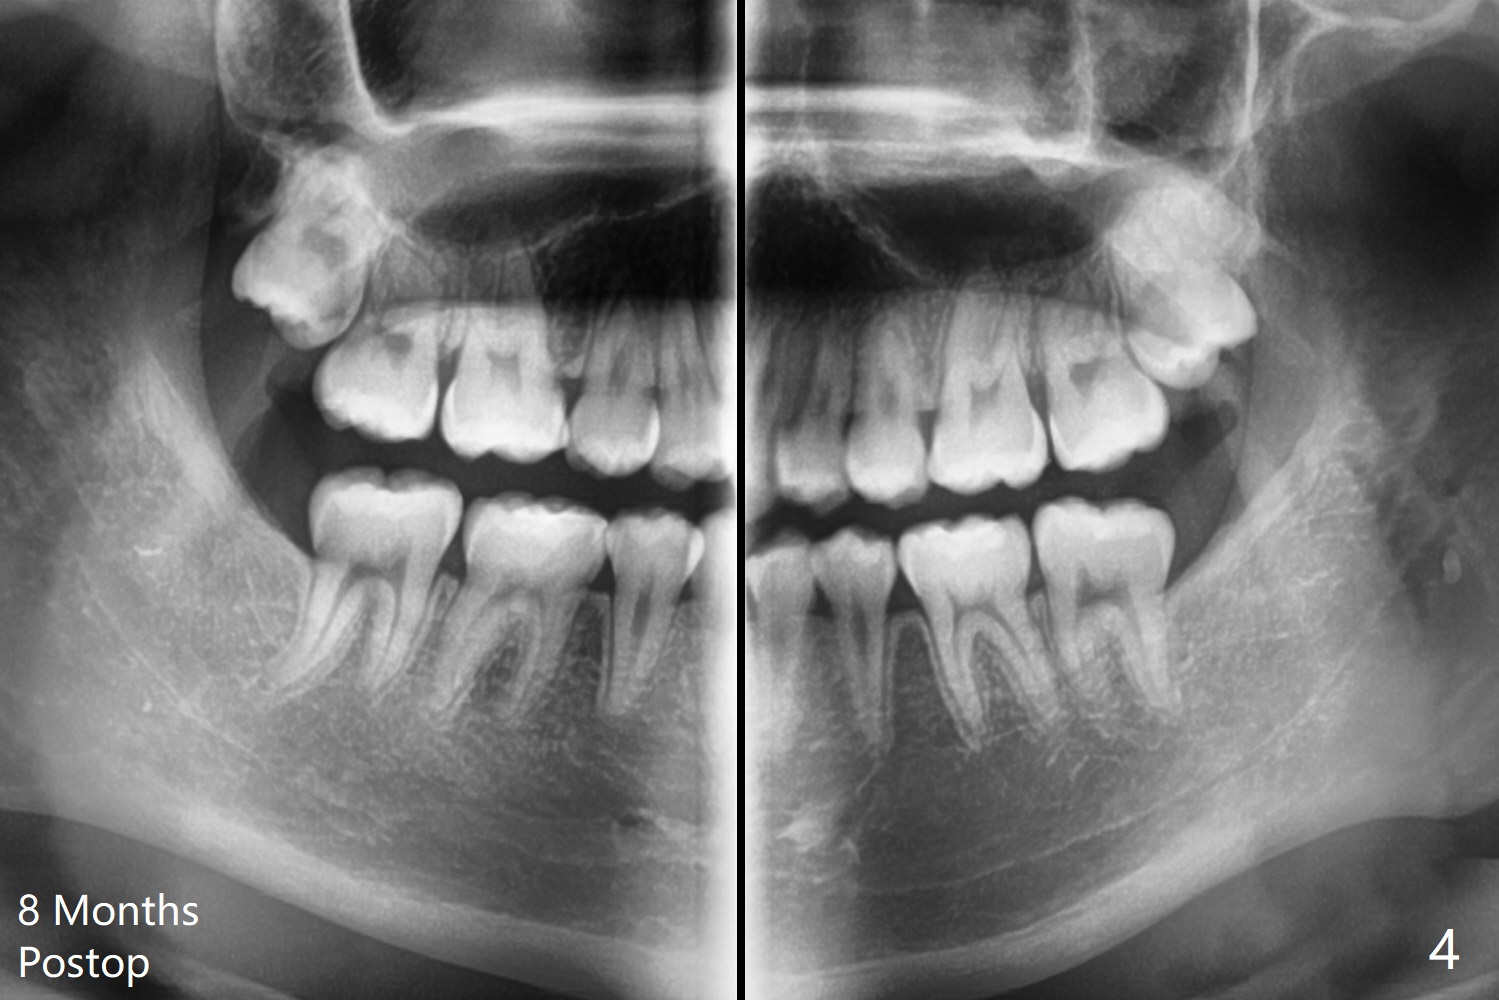

15岁男孩分离器使用后(图一:箭头)无法在左下7放置band,可能因为8阻生(图一,与图二对比)。1.5年后左下8萌出(图二),下颌8拔除,牙槽窝放置Osteogen Plug(图三),八个月后牙槽窝愈合(图四)。